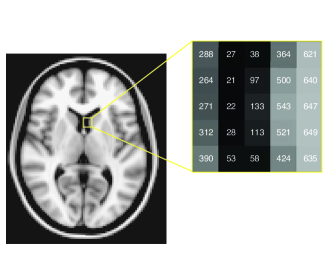

We now give a brief description of what a Magnetic Resonance Image is. This can be important in order to understand some basic characteristics of the random variables we are going to use. It is worthwhile to point out that some preprocessing is necessary in this type of image in order to take raw data from the scanner and prepare them for statistical analysis. Some of the steps usually applied in the image preprocessing are motion correction, slice timing correction, spatial filtering, intensity normalization, and temporal filtering. Here we are not going to explain those in detail, the interested reader can refer to Poldrack \BOthers. (\APACyear2011). In this case, an MRI can be viewed as a matrix of numbers that correspond to spatial locations. When we view an image, we do so by representing the numbers in the image in terms of grayscale values and each element in the image is called as a voxel, which is the three-dimensional analog to a pixel. See figure 1.1 for a visual description.

1.0.2 What is an fMRI experiment?